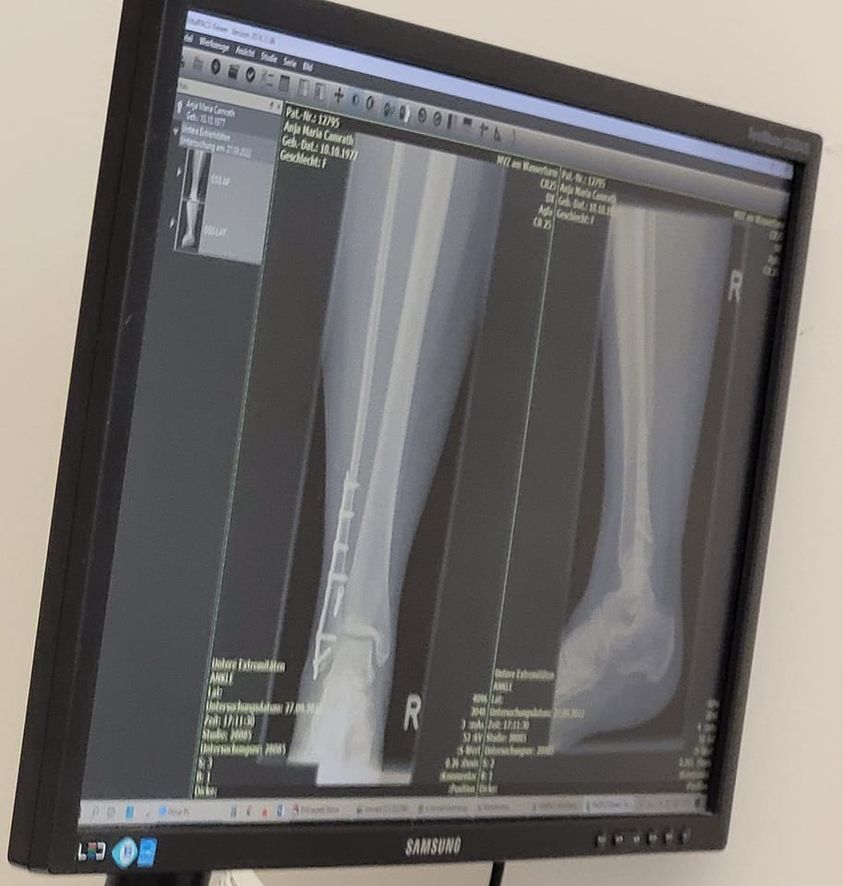

Flop:

- Wenn das Röntgenbild nichts geworden ist und du nochmal ein neues machen musst

- Wenn du das erste mal ohne Hilfe (Krücken) draußen läufst und das einfach mal super unangenehm ist

- Wenn dir nach dem Tag mit all der Action jetzt der Fuß weh tut, fail, haha

ABER....

Top:

- Ansonsten alles super, der Knochen ist genau da wo er sein soll und ist perfekt angewachsen. (Die Platte ist unten etwas lang, aber das lässt sich jetzt erstmal nicht ändern.) Ansonsten ist aber alles soweit in Ordnung. Physio für die Beweglichkeit und Belastung machen wir vorerst weiter und zwei Wochen bin ich auch erstmal noch krank geschrieben damit.

GebrochenerFuß27092022.jpg